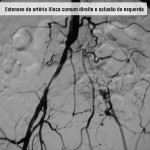

Doença obstrutiva segmento aorto ilíaco – Caso 01

Doença obstrutiva segmento aorto ilíaco – Caso 02